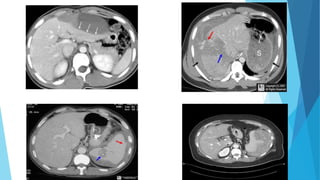

Abdominal Computed Tomography

 Abdominal CT is becoming the test of preference for evaluating

the abdomen of patients with blunt abdominal trauma who are

hemodynamically stable and complain of abdominal tenderness or

are unevaluable.

 It allows estimation of the amount of intra-abdominal fluid and

accurate imaging of solid parenchymal injuries in most patients.

 Abdominal CT plays a major role in the decision to manage the

injured spleen, liver, or kidney nonoperatively

 Abdominal CT has become the mainstay of imaging for the stable

blunt trauma patient and has led to the emergence of

Nonoperative management of many solid abdominal organ

injuries.

 Abdominal CT is typically performed with IV contrast timed to

capture the portal venous phase, which best demonstrates the

vasculature and visceral perfusion of the solid abdominal organs.

 CT provides excellent visualization of the solid organs, allowing

the characterization of injury severity (injury grade) and the

recognition of active bleeding, which appears as contrast

extravasation.

 The retroperitoneal structures are also well visualized on CT,

identifying injuries that are difficult to evaluate with FAST or

DPL

Case 1

 CT scan

 Positive or negative?????

 Treatment. Explain.